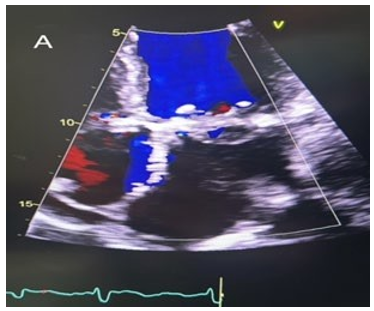

66 years old lady known case of hypothyroidism, hyperlipidemia, previous cerebrovascular accident that recovered, recurrent syncope attacks secondary to partial seizures and recent paroxysmal atrial fibrillation was referred for surgical evaluation. She was frail with history of cervical spondylosis. She had positive family history of ischemic heart disease affecting her brother and mother and she was non-smoker. Patient previously underwent Mitra Clip at another institute 1 year previously for severe degenerative mitral regurgitation (MR). The procedure at the time was uneventful with reduction of her mitral regurgitation to mild MR (Garde I). However, 6 months following the procedure she had increasing shortness of breath on exertion and later at rest with New York Heart Association class III/IV symptoms (NYHA class III/IV). She subsequently required two hospitalizations for heart failure over the next 4 months. Repeat transthoracic echocardiography showed severe recurrent MR with an anteriorly directed jet with prolapse of part of P2 and P3 segments (Figure 1 A).

Figure 1A: Pre-operative four-chamber view of transthoracic echocardiography showing severe mitral regurgitation.